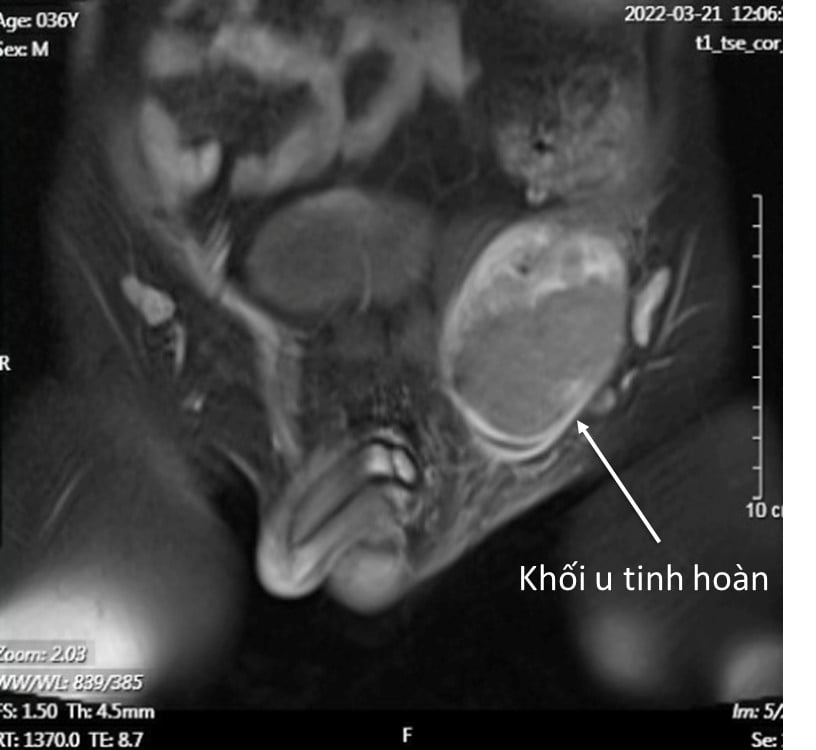

Hình chụp X-quang khối u tinh hoàn của bệnh nhân. Ảnh: BVCC.

Các bác sĩ phát hiện bệnh nhân bị khuyết một bên tinh hoàn trái, xuất hiện một khối cứng chắc, ấn đau tức vùng bẹn trái. Các xét nghiệm, hình ảnh chụp cộng hưởng từ sau đó cho thấy khối sưng này chính là tinh hoàn đã bị ung thư hóa.

Đáng nói hơn, khối u đã di căn tới nhiều vị trí vùng chậu và ổ bụng. Do đó, ông được chỉ định phẫu thuật cắt u tinh hoàn, nạo vét hạch và phải phối hợp điều trị hóa chất.